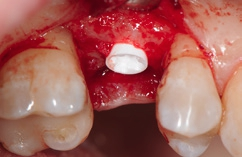

Unter Lokalanästhesie erfolgte nach krestaler Schnittführung die Aufklappung (Abb. 5) und die Aufbereitung des Implantatbettes gemäß dem chirurgischen Protokoll für NobelPearl mit den Bohrern des NobelPearl Surgical Tray. Nach Ankörnung mit dem Rosenbohrer wurde unter Beachtung der korrekten Implantatachse die 1. Bohrung mit dem zylindrischen Pilotbohrer Ø 2,3 mm auf die geplante Länge von 10 mm angelegt. Für die unterschiedlichen Längen stehen in der Folge formkongruente Profilbohrer zu Verfügung. So wird für die weitere Aufbereitung zunächst der Profilbohrer „small“, Länge 10 mm, Ø 3,3 mm (Farbcodierung violett), und danach der Profilbohrer „regular“, Länge 10 mm, Ø 4,2 mm (Farbcodierung gelb, hier mit Tiefenstopp), ausgewählt (Abb. 6).Da das NobelPearl-Implantat nicht selbstschneidend ist und beim Eindrehen des Implantats der Werkstoff Keramik keine Temperatur wie ein Titanimplantat ableitet, muss als letztes Instrument der Gewindeschneider auf die gesamte Implantatlänge eingesetzt werden.

Die Implantate wurden im Anschluss mit einer ausreichenden Primärstabilität von 30 Ncm und einem suprakrestalen Anteil 0,6 mm platziert. Diese suprakrestale Positionierung wird durch einen gegebenenfalls am Profilbohrer anbringbaren Tiefenstopp (Abb. 7) vereinfacht. Für das Einbringen der Implantate steht ein neues, zur „Inter-X“-Innenverbindung formschlüssiges Eindrehinstrument (Abb. 8) zu Verfügung, wodurch eine optimale Kraftübertragung während des Inserierens des Implantats gewährleistet wird (Abb. 9). Die Einheilkappen sind deutlich abgeflacht und ermöglichen einen einfachen primären Wundverschluss (Abb. 10 und 11). Im vorliegenden Fall verlief die Wundheilung komplikationslos. Nach einer auch für Keramikimplantate heute üblichen Einheilungszeit von 3 Monaten zeigten sich die Implantate in der Röntgenkontrollaufnahme stabil osseointegriert (Abb. 12). Es fanden sich an beiden Implantat-Loci entzündungsfreie Weichgewebsverhältnisse, woraufhin mit der prothetischen Versorgung des Implantats begonnen werden konnte.